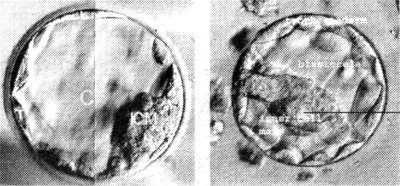

Embrião

com cinco a seis dias |

|

|

|

células

estaminais |

5. Se o objectivo é

fazer clonagem terapêutica, o embriã6 é destruído, ao serem

colhidas as células estaminais que se podem transformar em todos

os órgãos e tecidos. De futuro, espera-se poder criar em laboratório

órgãos para transplantes.